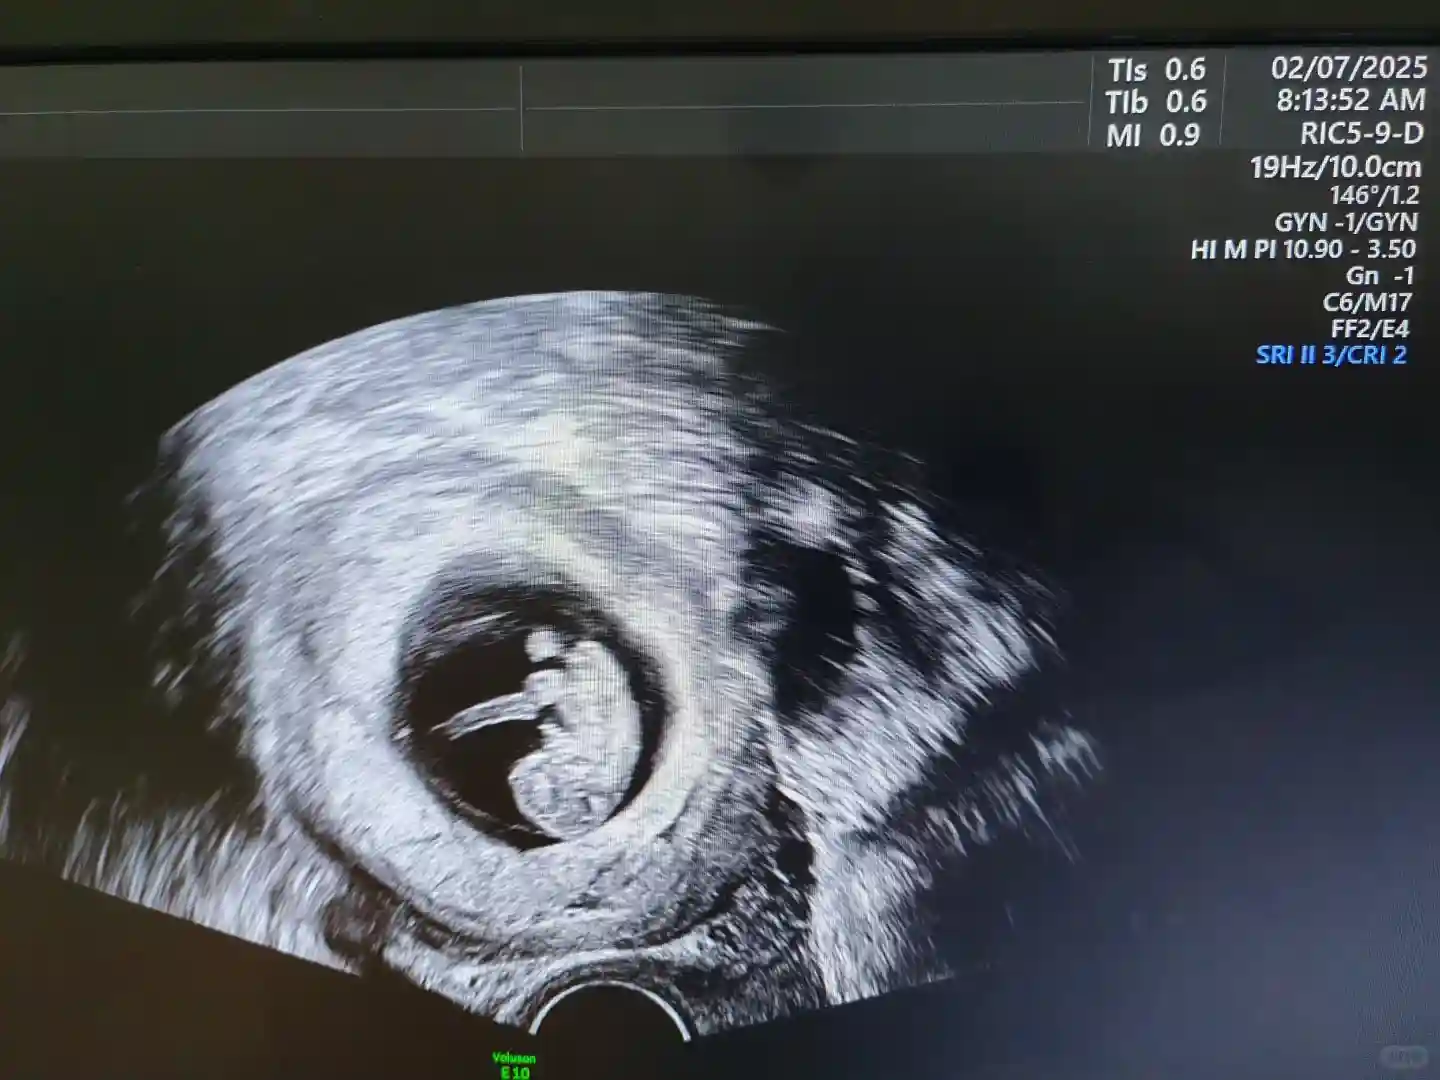

IVF助孕,采用卵泡期长方案,取卵10枚,成熟卵子6枚,正常受精分裂只有2枚胚胎,有四个多精受精(可能和卵子质量有关系),最后成胚两枚胚胎(7C/II 8C/II),移植成功怀孕,现怀孕9周,胎心好。

IVF助孕,采用卵泡期长方案,取卵10枚,成熟卵子6枚,正常受精分裂只有2枚胚胎,有四个多精受精(可能和卵子质量有关系),最后成胚两枚胚胎(7C/II 8C/II),移植成功怀孕,现怀孕9周,胎心好。 三促进行中 基础卵泡一颗 调理到三颗 北塞浦路斯供卵